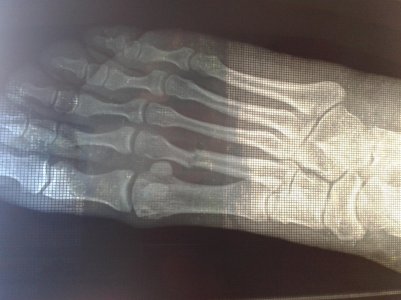

Здравствуйте, доктор! Прошу не отказать мне в консультации по перелому второй плюсневой кости (насколько это возможно в рамках данной темы)

20150703_141553.jpg20150703_141434.jpg20150703_141819.jpg20150703_141646.jpg

Травма случилась 18 мая 2015 от падениы с лестницы. Сразу обратились в травмпункт по месту. Снимок. Перелом со смещением. Дежурный хирург сказал, что смещение в пределах допустимой нормы, поэтому вправлял вручную (вроде как довольно не плохо вправил). Наложили лангету, прописали кальций и сказали явиться на снятие через 4 недели. 20 дней с момента травмы передвигалась только на костылях. По истечении 3х недель начала по-тихоньку пробовать ходить с опорой на пятку прям в лангете. Спустя 4 недели явилась к врачу, как и было сказано. Сначала сняли лангету, потом отправили на контрольный снимок. Результат: кость несколько сместилась, образование мозоли не видно. Снова накладывать гипс не стали, а лишь сказали породолжать пить кальций и бинтовать стопу эластичным бинтом. Нагрузку на пятку разрешили давать дозированную. Сегодня с момента травмы прошло 6 недель. Есть жалобы на отечность ноги после 3-х часовой нагрузки, а так же на изменение больной ноги в цвете - она по сравнению со здоровой выглядит темнее и с оттенком синевы. А так же присутствует щелчок в области перелома если пошевелить пальцами "вверх-вниз". Но я заметила, что этот самый щелчок отсутствует утром и появляется лишь после того, как немного похожу. Продолжаю бинтовать ногу, ходить с опорой на пятку. Хожу достаточно много, т.к у меня маленьки ребенок, за которым нужен постоянный контроль. Поэтому, на ногах я практически с утра до вечера (днем удается полежать 3 часа пока ребенок спит). Помочь сечас физически мне некому. Всвязи с изложенным у меня есть несколько волнующих вопросов: Насколько серьезно смещение? Могут ли быть плохие последствия от столь большой нагрузки на ногу? И насколько тревожен щелчок в области перелома? Возможно есть на снимке хоть какой-то намек на образование мозоли? И почему нога отличается по цвету? Прошу поостить меня за такое кол-во вопоосов. Просто я живу сечас в селе и пока не имею возможности добраться в город к врачу. Доп.информация: Возраст 30 лет, вес 53 кг, рост 166 см. Спасибо Вам!

Фото загрузились в следующем порядке: первая верхняя и снизу под ней - контрольный результат спустя 4 недели. Вторая сверху - сразу после перелома. Третья сверху - сразу после вправления. Благодарю Вас!

Замедленное сращение перелома, нужны ортопедические стельки с выкладкой поперечного свода и удобная обувь, синюшность со временем уйдет, перелом может быть срастется и перестанет щелкать.